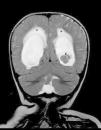

Radiología Solución del caso 30. Papiloma de los plexos coroideos con realce meníngeo

Solución del caso 30. Papiloma de los plexos coroideos con realce meníngeo

Solution to case 30. Choroid plexus papilloma with meningeal enhancement